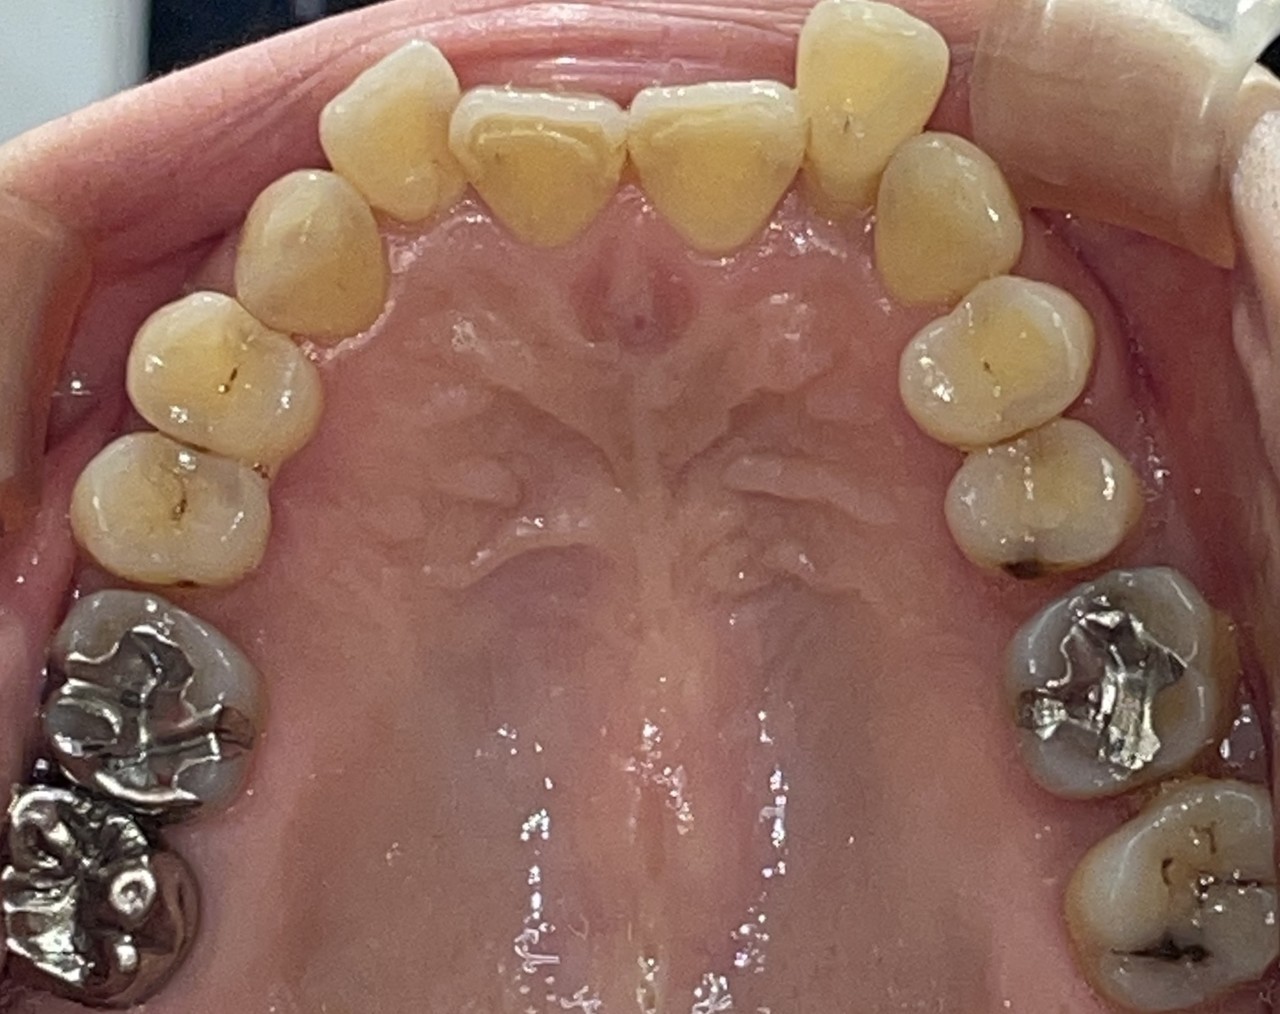

Before

After

矯正の種類 / invisalign GO

年齢・性別 / 40代女性

主訴  /  叢生

治療期間 / 12ヶ月

費用 / 簡易検査 5,000円(税別) 精密検査 30,000円(税別)

両額マウスピース 450,000円(税別)  両額リテイナー料 60,000円(税別)

※マウスピース交換時別途調節料3,000円(税別)

副作用 / 口内炎・歯の移動に伴う痛み・知覚過敏 ※数日で収まる場合が多いです

リスク / 後戻り防止の為、夜のみマウスピースで保定を指示